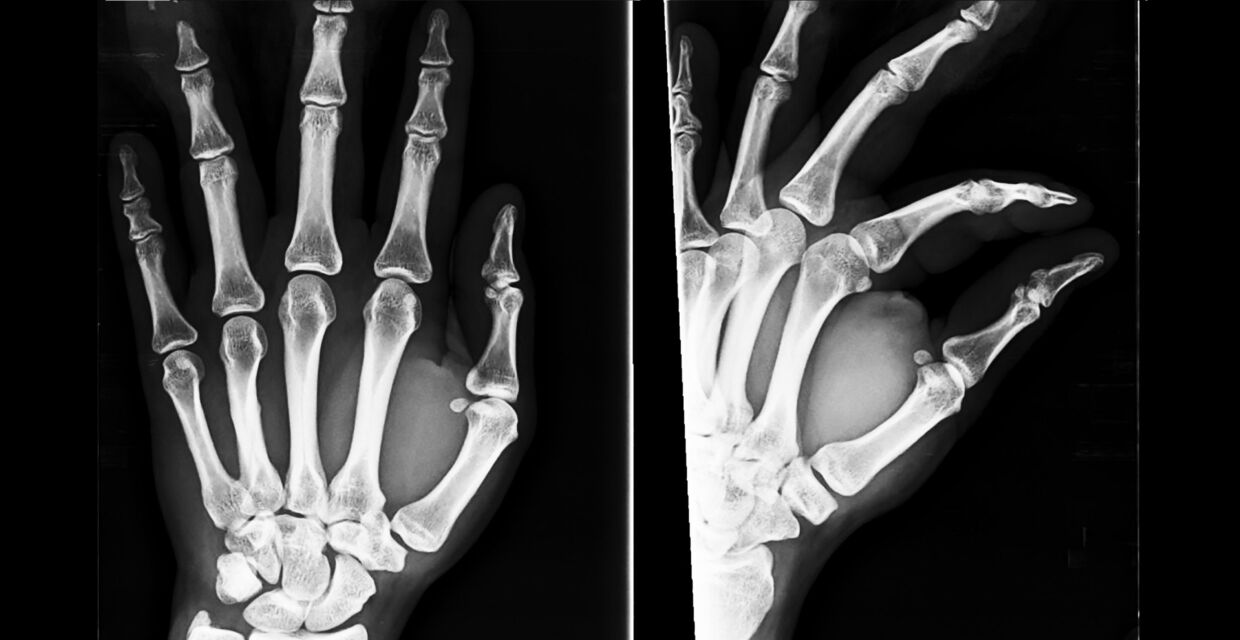

Scaphoid fractures can be difficult to identify as they do not usually cause significant swelling or bruising. If a fracture is suspected then an x-ray should be requested.

Diagnosing a scaphoid fracture can be difficult as they do not usually cause significant swelling or bruising. When presenting at your GP or at the Emergency Department following your injury, it is important that the medical professionals who are dealing with you takes a detailed account of what has happened and what symptoms you are experiencing. If a scaphoid fracture is suspected then an x-ray should be requested.

It is known that scaphoid fractures are not always visible on x-rays carried out shortly after the injury. If the x-ray does not show a fracture to the scaphoid bone, but the clinical picture does suggest a fracture, then the medical professionals should manage the patient as having a suspected fracture.